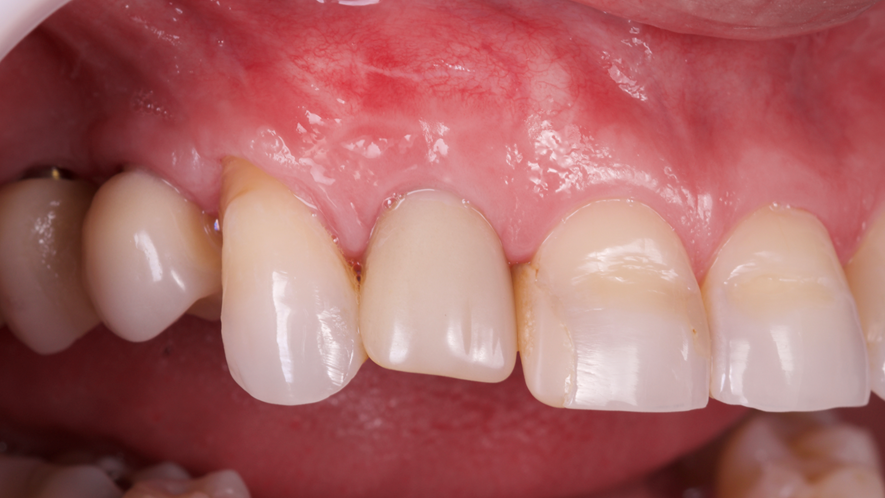

Este trabalho tem como objetivo relatar um caso clínico de exodontia minimamente invasiva de um incisivo lateral superior com fratura radicular, realizando implante imediato em alvéolo pós-extração, enxerto de tecido conjuntivo subepitelial e osso bovino liofilizado para preenchimento de GAP, prontamente à instalação de pilar reto e provisório imediato.